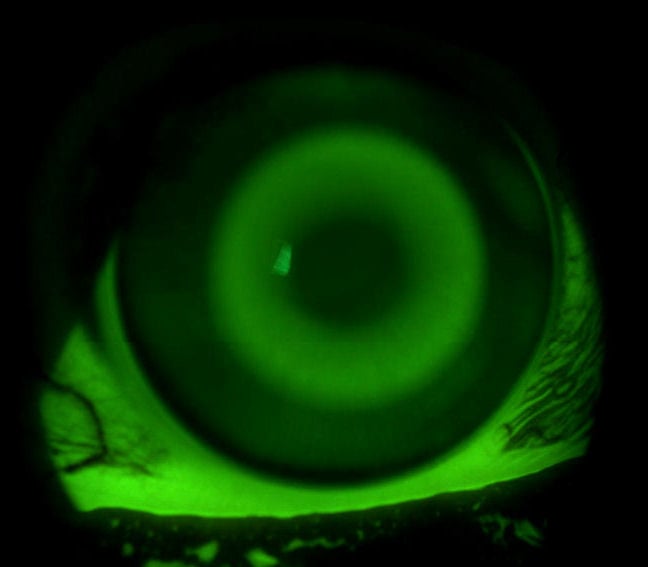

Contex OK®-EX Myopia Management Design

The Contex OK®-EX design is the result of years of research and development. With the advent of myopia control and the desire to quickly reduce larger amounts of myopia, Contex set out to create a lens that would offer the advantages of a controlled tear layer in the reverse zone and the ability to reduce higher amounts of myopia quicker and with more control.

Contex OK® E-System

Contex OK® E-System lenses set the standard for overnight orthokeratology by offering the most advanced topography based fitting as well as empirical, trial or dispensable inventory sets. With no age restrictions, the Contex OK® Lens is the perfect option for active kids and teens that aren’t eligible for refractive surgery.